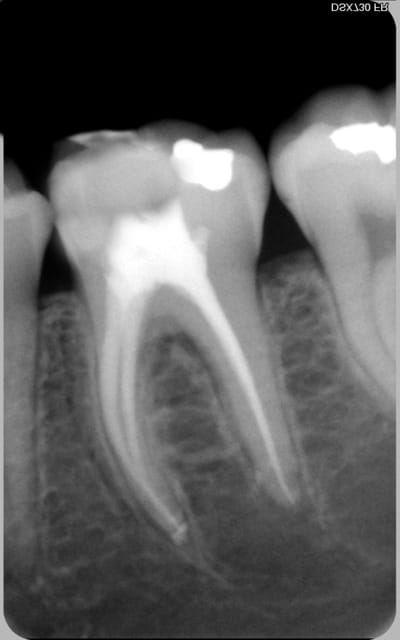

encore des radios,peut-etre assez moyen comme traitement...mais je vu pire...

les dernieres radios. patient en urgence ,abces... il voulait pas extraire la dent. j'ai lui bien explque et il a choisi de essayer de garder la dent. retrait,pas d'isolation avec la digue donc pas de tenon fibree,amalgam et screw post.traitement fait il ya 2 ans je crois.patient fidel de cabinet maintenent.

j'ai jamais utilise en roumanie l'amalgam et ca s'utilise pas du tout dans le cabinet du roumanie.